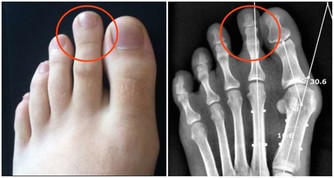

其實,痔瘡、肛裂、直腸癌都會出現便血的症狀,症狀相似,很容易誤診。也造成了許多患者在出現肛腸問題時,當做痔瘡自行治療,致使許多肛乳頭瘤、直腸息肉、甚至直腸腫瘤患者錯過治療的最佳時機。

所以當發現大便帶血時,最好去醫院外科做直腸指診,可以在很大程度上發現是否患有直腸癌。若大便中有血、黏液,大便習慣改變,腹瀉與便秘交替出現,最好去做結腸鏡,千萬不要有僥倖心理。